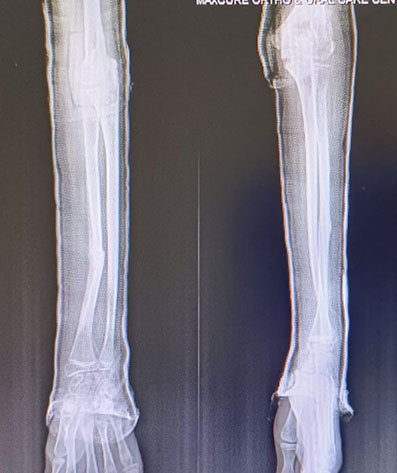

X-ray Post Injury

The Challenge: A Displaced Both-Bone Fracture

The patient’s fracture had significant displacement and angulation, often mandating surgery (ORIF) globally. Surgery risks damage to the active growth plates (physes) and requires hardware removal later. Our decision was guided by the child’s immense healing potential.